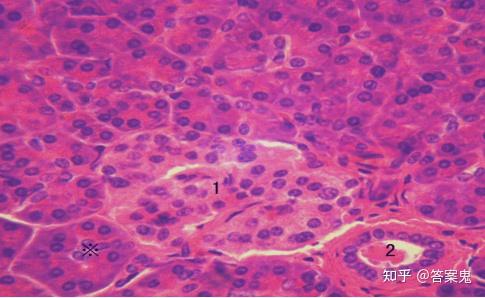

6,胰腺:浆液性腺泡(泡心 细胞),胰岛

周围染色深的是浆液性腺泡,大小不等,单层腺细胞围成,腺腔不明显,有些